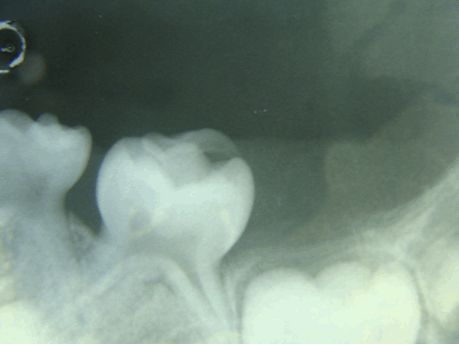

The ground section of the specimen showed a structure resembling a small, single rooted tooth. The specimen showed enamel, dentinal tubules within the dentin and the dentino-enamel junction. A thin layer of cementum was seen at the periphery. These features are suggestive of compound odontoma (Figure 5).

Cursor on image to zoom/Click text to open image

Figure 5: Ground section showing enamel, dentin, dentino-enamel junction and a thin layer of cementum at the periphery.